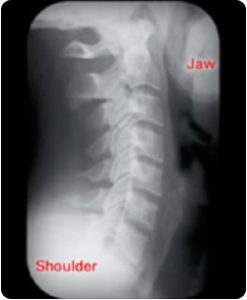

Poco después del descubrimiento de los rayos X, los quiroprácticos empezaron a utilizar esta herramienta en el examen y el cuidado de la columna vertebral. Además de revelar la presencia o ausencia de las curvas adecuadas en la columna, la vista lateral de la columna puede mostrar con más facilidad los efectos a largo plazo de un trauma espinal que no se haya corregido.

Aunque este proceso puede ocurrir en cualquier parte de la columna vertebral, es más fácil de ver en la columna cervical (cuello). Así es como la vista lateral del cuello debería verse. Desde el lado, el cuello debe tener una elegante curvatura hacia adelante. Los bordes de cada hueso están bien definidos. Debe haber el mismo espacio discal entre cada hueso y las aperturas de las raíces nerviosas deben ser claras y sin obstrucciones.

Esto sería considerado una curvatura «normal» del cuello visto lateralmente.